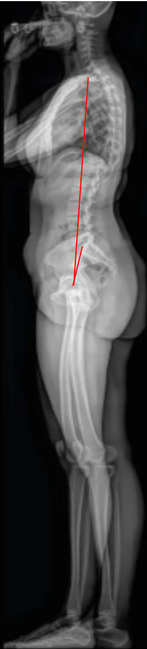

T1 Pelvic Angle (T1PA)

The T1 Pelvic Angle (T1PA) is a composite radiographic parameter that evaluates global sagittal alignment by incorporating both spinal inclination and pelvic retroversion into a single angular measure.

It is defined as the angle between two lines: one drawn from the center of the T1 vertebral body to the center of the femoral heads, and the other from the center of the S1 endplate to the center of the femoral heads.

Unlike the Sagittal Vertical Axis (SVA), which is highly dependent on patient positioning, the T1PA provides a posture-independent assessment of sagittal alignment and is thus a more reliable marker for overall spinal balance.

An increased T1PA corresponds to greater anterior spinal inclination and compensatory pelvic retroversion — key indicators of positive sagittal imbalance.

• Line 1: from the center of T1 to the center of the femoral heads.

• Line 2: from the center of S1 endplate to the center of the femoral heads.

• Measure the angle formed between these two lines — this is the T1 Pelvic Angle (T1PA).